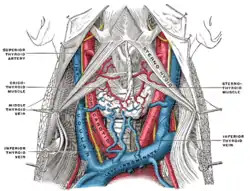

The internal carotid and vertebral arteries. Right side. (Superior thyroid visible at center.) The thyroid gland and its relations.

The thyroid gland and its relations. Side of neck, showing chief surface markings.